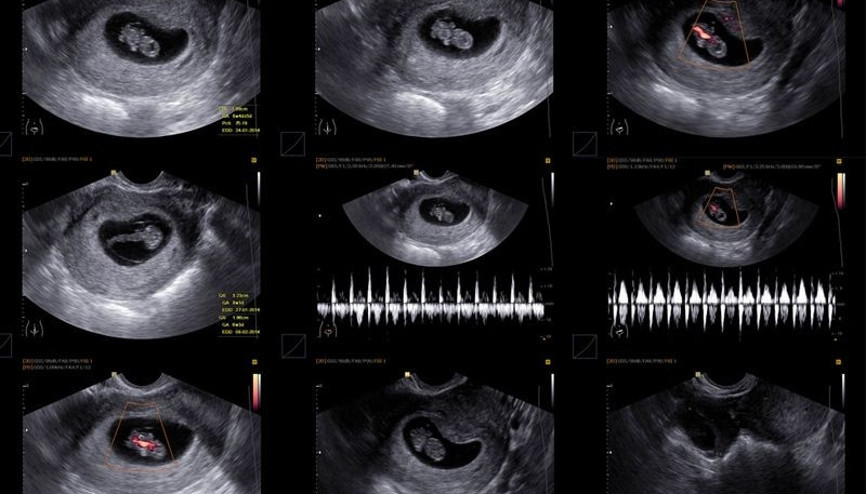

Gebelik kesesi, bebeğin varlığının en önemli kanıtı olarak çiftler için merakla beklenen bir oluşumdur. Hamilelik süresi boyunca bebeğin geliştiği yer olan gebelik kesesi ne zaman, kaçıncı haftada gçrülür? İşte gebelik kesesi hakkında merak edilenler…

#GebelikGebelik kesesi embriyoyu saran sıvı boşluğuna verilen isimdir. Rahim içerisinde bulunan bu kese embriyonun tanımlanmasından önceki süreçte gebeliğin belirlenmesi için oldukça önemlidir. Gebelik kesesi hamilelik süresince bebeğin gelişimin gerçekleştiği bölge olması sebebiyle oldukça önemlidir. Bazı durumlarda boş gebelik kesesi oluşabilir. Bu durumda kese oluşumu gerçekleşse de embriyo oluşumu yoktur.